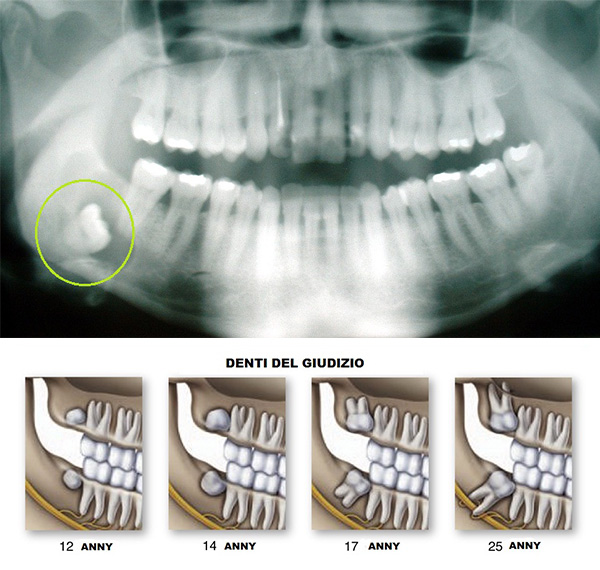

Denti del guidizio

Il terzo molare è meglio conosciuto come "dente del giudizio". E' l'ultimo dente a spuntare solitamente tra i 17 e i 25 anni. Accade però spesso che il dente del giudizio rimanga incluso, senza sbocco.

Il dente è incluso quando manca spazio nell'arcata dentale e la sua crescita ed eruzione sono impediti dalle gengive, dall’osso o da un altro dente.

Non necessariamente, la situazione risulterà chiara dalle informazioni fornite dalla panoramica dentale. Purtroppo non tutti i problemi collegati al terzo molare sono dolorosi o visibili. Con il tempo le radici diventano lunghe e risulta più difficile estrarre il dente . Se riconoscete i sintomi, vi consigliamo di reagire rapidamente per evitare complicazioni.